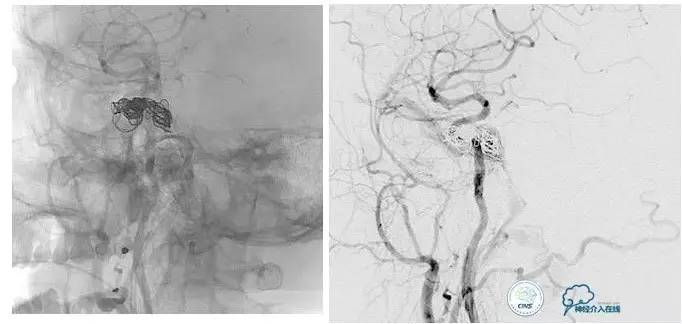

海绵窦区DAVF,颈内外均参与供血。

采用净买入路,经岩下窦栓塞。

首先放入少量弹簧圈,给Onyx提供框架。

开始注入Onyx时,在颈内动脉内放入保护球囊,防止意外进入颈内动脉内。

栓塞后胶的透视影像。

最终结果,DAVF完全消失。